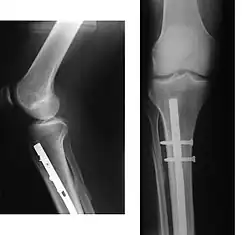

Эндопротезирование суставов

При наличии показаний к операции методом выбора может быть эндопротезирование суставов. В настоящее время разработаны и успешно применяются эндопротезы тазобедренного и коленного суставов. При остеопорозе эндопротезирование осуществляется конструкциями с цементным креплением. Дальнейшее консервативное лечение коленного сустава способствует снижению сроков реабилитации оперированных больных и повышению эффективности лечения.